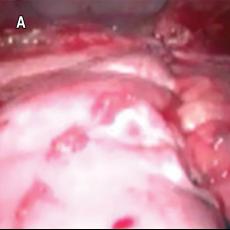

Plastía diafragmática y pleurodesis química por videotoracoscopia: una alternativa como tratamiento quirúrgico en paciente con hidrotórax hepático

Rodríguez-Blanco, José Antonio1; Acevedo-Pérez, Yulieth1; Rodríguez-Blanco, Jonathan1; Remolina-Medina, Carlos1